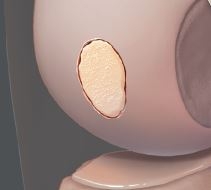

Articular Cartilage Defect

Cartilage defect of medial femoral condyle